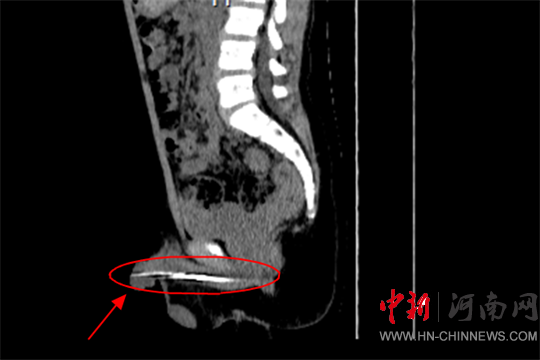

經(jīng)過詳細檢查

確認鋼針大概8-9公分

卡在了尿道內(nèi)